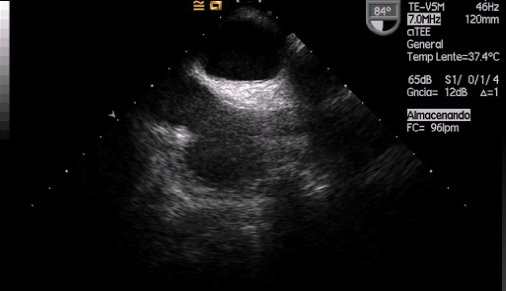

Curso de ecografía crítica en todas sus modalidades (ecocardiografía transtorácica y transesofágica, ecografía pulmonar, vascular, cerebral, FAST) dirigido a: médicos intensivistas, emergenciólogos, anestesiólogos, internistas, médicos de familia, neumólogos, cardiólogos y a todo aquel interesado por utilizar la ecografía como parte del examen físico del paciente crítico.

En nuestro afán por seguir el trabajo empezado hace ya varios años desde Europa (España) por impulsar la ecografía crítica para intensivistas, emergenciólogos, anestesistas, internistas, subespecialistas de obstetricia crítica, neumólogos y todo aquel médico interesado en aprender a utilizar la ecografía como parte de su examen físico, ahora desde Centroamérica (Panamá), hemos escrito el primer libro Latinoamericano-Europeo de ecografía crítica sub-especializado y dedicado exclusivamente al paciente con shock de cualquier etiología (obstructivo, distributivo, cardiogénico, hipovolémico) que involucra todas las modalidades ecográficas: ecocardiografía, ecografía pulmonar, vascular, abdominal, del sistema nervioso central/doppler transcraneal, etc) en el que participan muchos expertos en sus respectivas áreas tanto de Europa como de América y también algunos profesores del EDEC (Diploma Europeo de ecocardiografía / ESCIM- Sociedad Europea de Medicina intensiva).